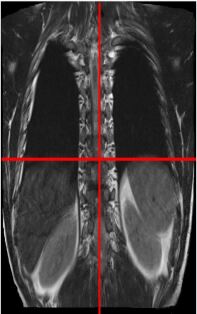

Figure 5: Complete 3D visualization for a human spine after joining the eight 3D sub-images: (a) Anterior view, (b) Posterior view [a,b,c,d,e,f,g,h marked on this figure corresponds to the sub-images in Figure 4]

Initially, the 2D2𝐷2D slices are split in 4 sub parts as shown in Figure 2 for a human spine, and the data set in divided in two parts. We use single instruction multiple data architecture using 8 logical cores. In parallel, for each block of sub-image, a 3D3𝐷3D matrix is created which is filled with the corresponding data leaving the specified slice gap in between slices as specified for each set as shown in Figure 3. Then edge preserved kriging interpolation is used to generate the 3d subimages. If we want to visualize these sub-images, then we can apply marching cube with color map and visualize the images as shown in Figure 4 and the complete 3D image for visualisation of full spine is as in Figure 5.